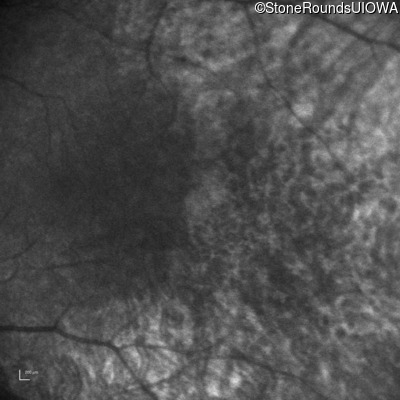

Infrared Fundus Photograph - Right -

No Light Perception

Infrared Fundus Photograph - Left -

Light Perception